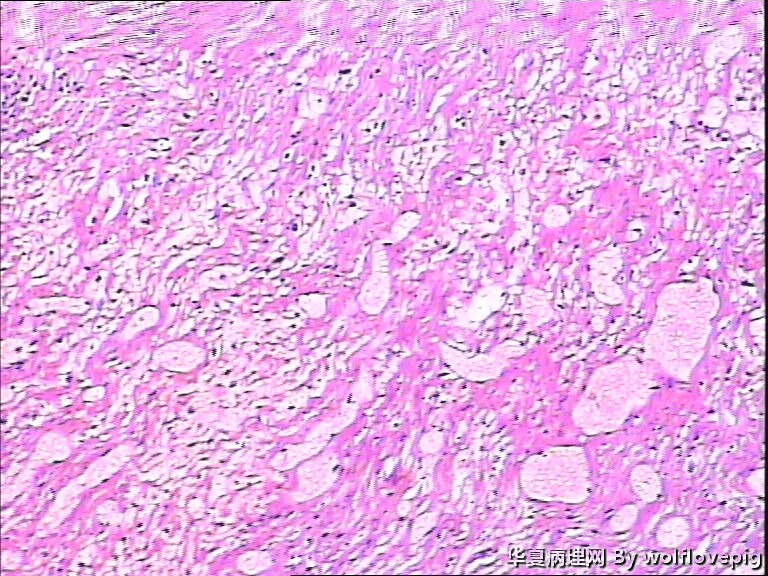

37y,肌壁间可见多个小结节0.2~0.8cm。